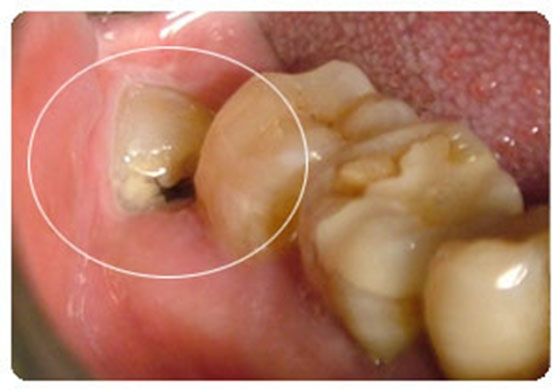

2、龋病。如果口腔内有蛀牙(龋齿),应该及时补牙,当浅龋、中龋的时候,没有不适症状,往往被忽视,在怀孕过程中,龋齿可能会发展为深龋,甚至牙髓炎。当深龋的时候,当食物进入牙洞后,容易引起明显的刺激痛;如果发展到牙髓炎,疼痛就非常明显了,无需刺激,牙齿会不定时的疼痛,尤其晚上疼痛更加明显,半夜因为牙疼来医院就诊的孕妇大多就是这种情况。